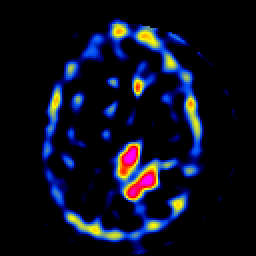

SPECT TL Study #8 -- Slice #35